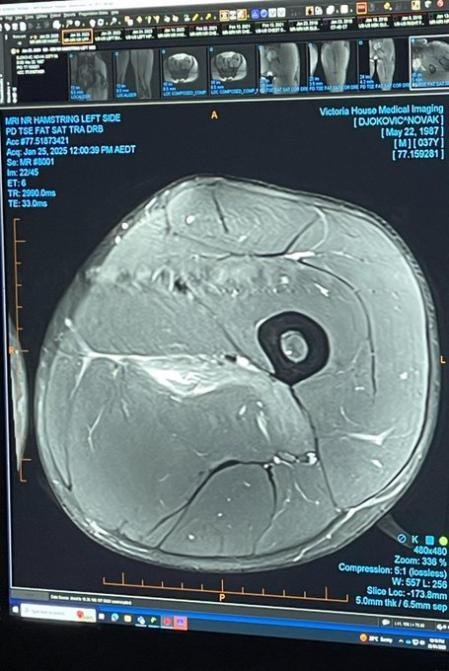

REDACCIÓN DEPORTES.- El tenista serbio Novak Djokovic colgó este sábado en sus redes sociales la imagen de la resonancia magnética a la que se sometió, como prueba de la lesión que padece en la pierna izquierda y que le obligó a retirarse de la semifinal del Abierto de Australia ante el alemán Alexander Zverev.

«Pensé en dejar esto aquí para todos los ‘expertos’ en lesiones deportivas que hay por ahí», es el texto con el que Djokovic ha acompañado el resultado de la resonancia con el fin de responder a aquellos que pusieron en duda que estuviera lesionado.